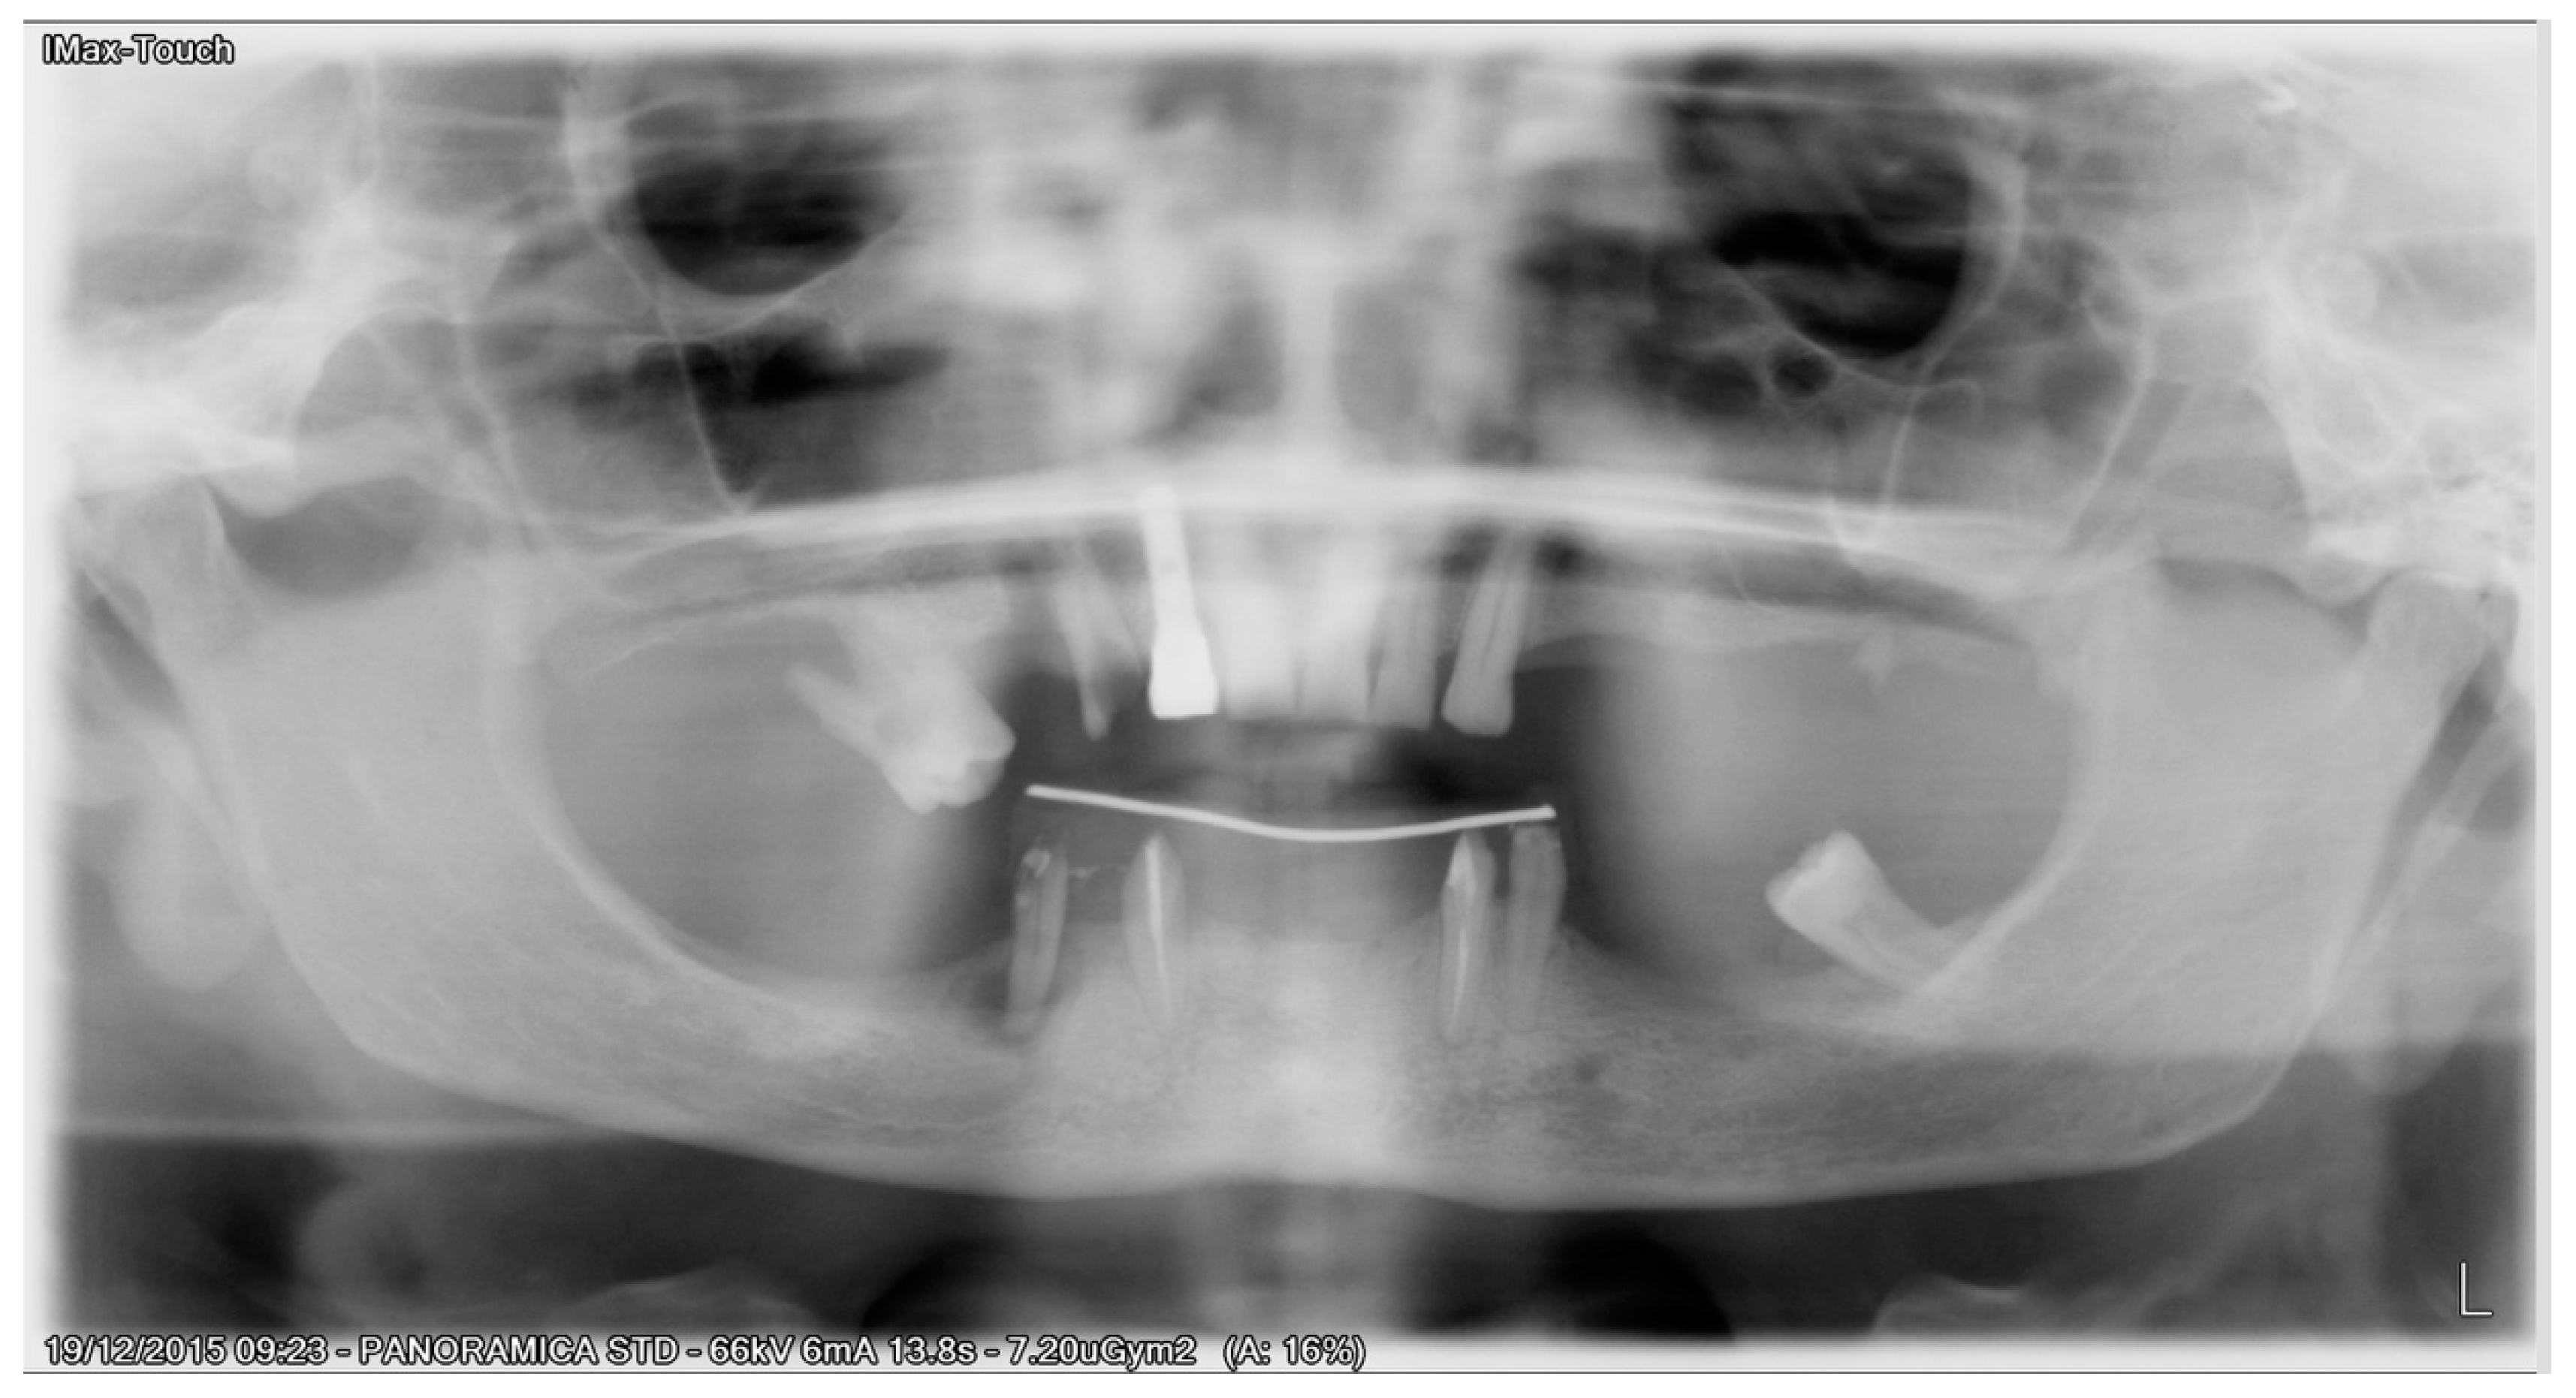

All patients received implants with a grit-blasted and acid-etched surface (Ossean®; Intra-Lock International®, Inc., Boca Raton, FL, USA) that were placed using a sterile surgical technique, as recommended by the manufacturer. Maximum care was taken to place the implants, regardless of whether they were inserted in an edentulous ridge or an extraction site, with a minimum insertion torque of 35 Ncm and not exceeding 50 Ncm (Figure 3).

Figure 3. Implants were inserted, and flat abutment connected.